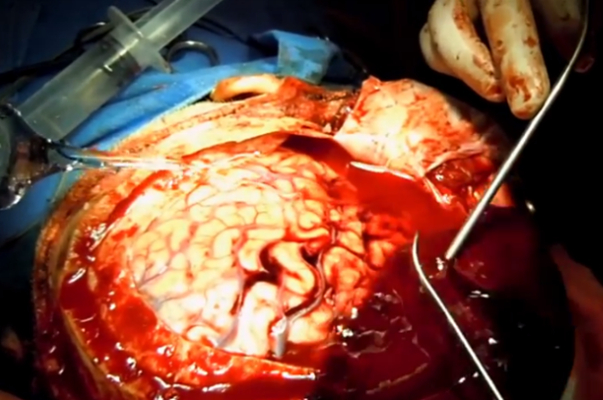

顱內血腫圖片

硬膜下血腫 (48)

硬膜下血腫 (49)

硬膜下血腫 (5)